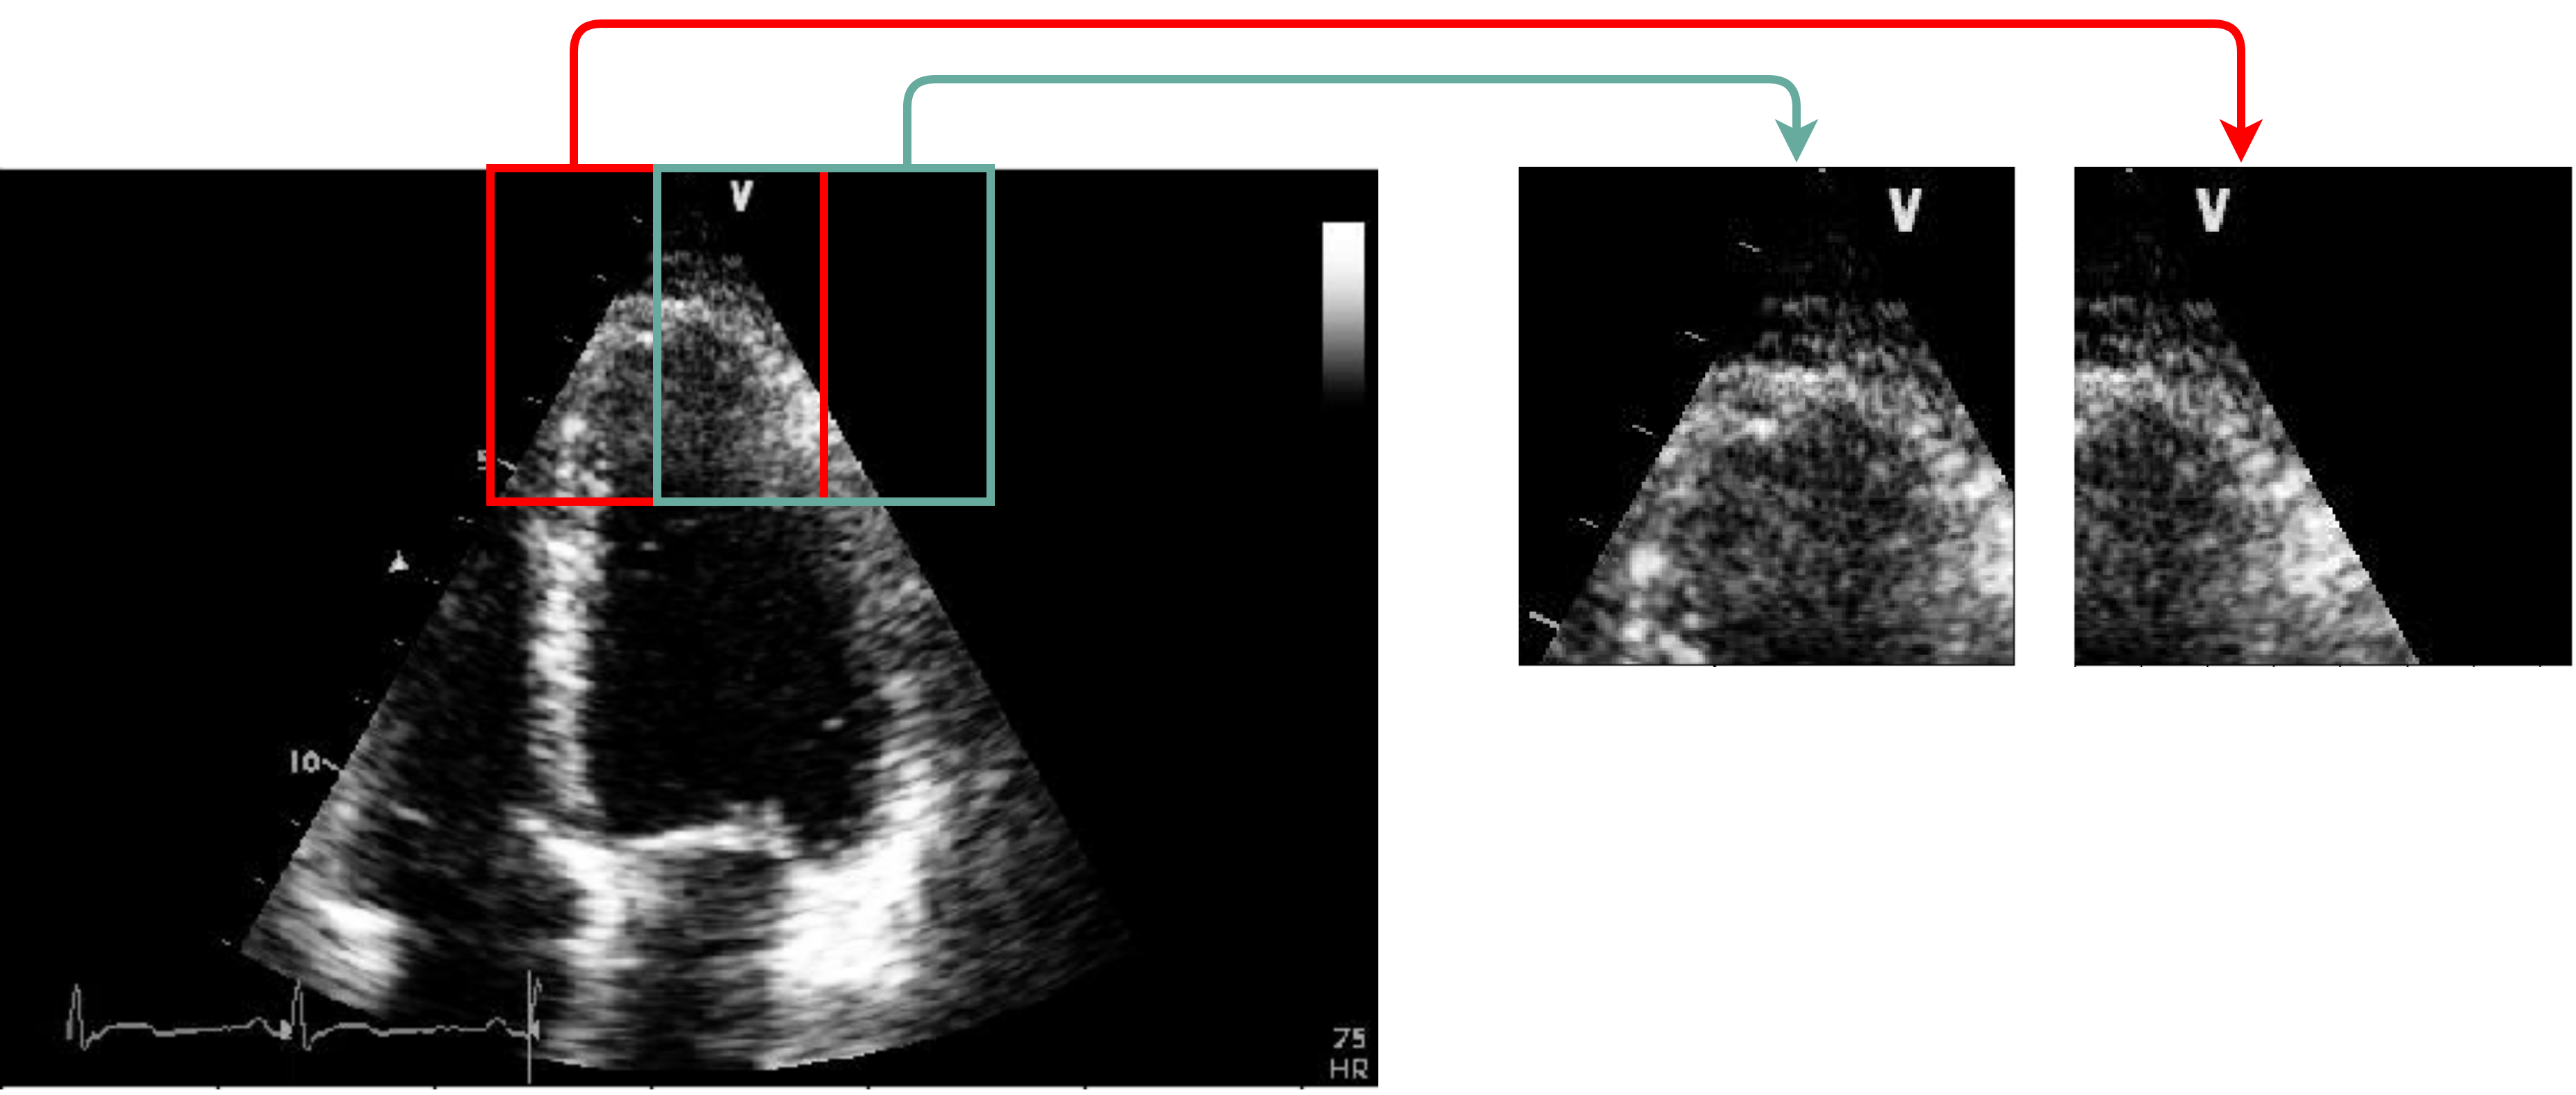

Figure 3 represents captured frames representing the quality of several videos from our dataset, which varies from good to noisy. Figures from 3(a) to 3(f) correspond to distinct frames each captured from different videos. We notice that in Figure 3(a) the left wall of the LV is blurred. Also, in Figure 3(b), the left wall of the LV is blurred and almost missing. In the same way, we observe that the totality of the LV wall is blurred in Figure 3(c); and that the interior of the LV is disrupted with noise in Figure 3(d). Finally, both Figure 3(e) and Figure 3(f) show acceptable LV representations, where the LV walls are captured and the chamber’s interior is empty from noise. Moreover, since our study is centered on the LV chamber only, we purposely ignore the distortions of the rest of the cardiac chambers (Right Ventricle, Left Atrium, and Right Atrium) in the dataset videos. For example, in Figure 3(e), both the Left Atrium and the Right Atrium are partially cut from the view, however, this does not impact our study.

Refer to caption

(a)

(b)

(c)

(d)

(e)

(f)

Figure 3: Captured frames from 6 different videos of our dataset, where each image from 3(a) to 3(f) corresponds to a distinct video. 3(a) represents a blurred left wall in the LV, 3(b) represents a missing left wall in the LV, 3(c) represents blurred LV walls, 3(d) represents noise inside the LV, and 3(e) and 3(f) represent normal echocardiograms